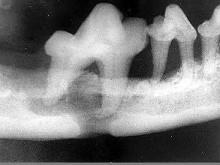

颌面外伤患者,咬合错乱,下唇麻木张口受限,经X 线检查如图。应该为 ( )

A上颌骨骨折

B颧弓骨折

C牙槽突骨折

D下颌骨骨折

E颧骨骨折